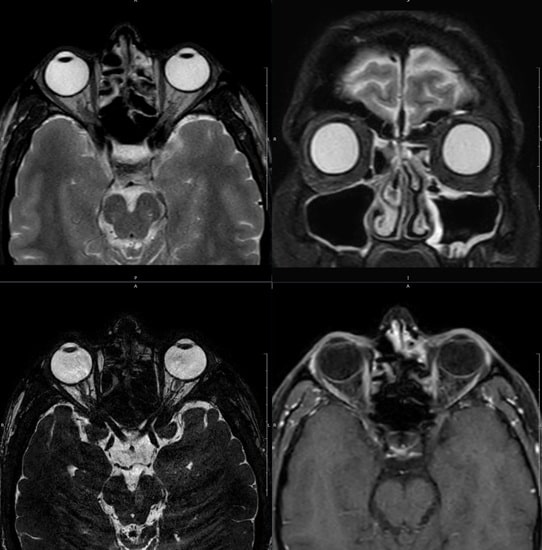

Ressonância magnética de órbitas: quando é indicada e o que o exame pode diagnosticar

A ressonância magnética de órbitas é um exame essencial em caso de dor ocular e outras doenças das estruturas da cavidade orbital.